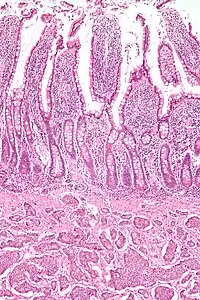

| Picture of a carcinoid tumour that encroaches into lumen of the small bowel. Pathology specimen. The prominent folds are plicae circulares, a characteristic of small bowel. | |

- Carcinoid tumors of the midgut – this is a type of neuroendocrine tumor (NET). They tend to be slow growing and are the most common type of small intestine tumor.